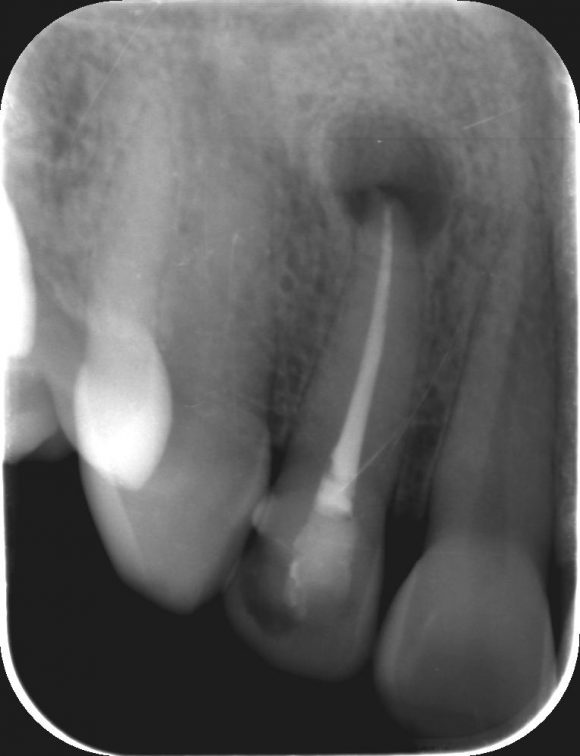

2. Gyökércsúcs rezekció – Így történik a fogciszta eltávolítása

1. Néhány nappal a gyökérkezelést követően a rezekciót is el kell végezni, ami a steril előkészületekkel és a receptírással együtt is kb. 60 perc alatt kényelmesen elvégezhető.

2. A helyi érzéstelenítés beadása után az ínyen bemetszést ejt az orvos, majd szabaddá teszi a csontfelszínt. Szájsebészeti fúróval egy kisebb csontablakot készít, melyen keresztül eléri a foggyökér csúcsát, valamint a cisztát.

3. A ciszta eltávolítása lépésről-lépésre történik, ügyelve arra, hogy annak hámbélését is teljesen kiszedje az orvos, mellyel megelőzzük a probléma kiújulását.

4. A gyökér „csúcsa” a csontablakon keresztül, úgynevezett retrográd gyökértömést kap, ami a gyökér amputált végének speciális lezárását jelenti.

5. A Clinidentnél arra is lehetőség van, hogy szükség esetén a csonthiányt csontpótló anyaggal töltsük fel, ezzel visszaállítva annak eredeti állapotát. Gyakran még a fog eltávolítása sem szükséges, hiszen nélküle is megoldható a ciszta teljes eltávolítása.

6. A műtét végén a sebet varratokkal látják el és antibiotikumot ír fel az orvos.

A rezekció nem más, mint a gyökércsúcsnak a cisztával együtt történő eltávolítása. Így megőrizhető a saját fog, a beteg szövetektől pedig megszabadulhatunk. A beavatkozás helyi érzéstelenítés mellett történik és teljesen fájdalommentes.